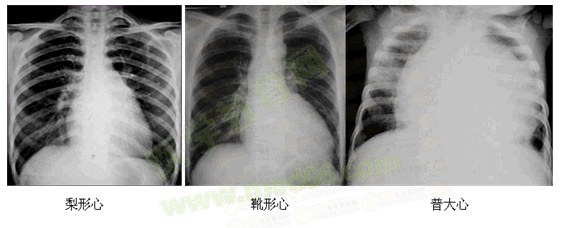

心脏大小

心脏